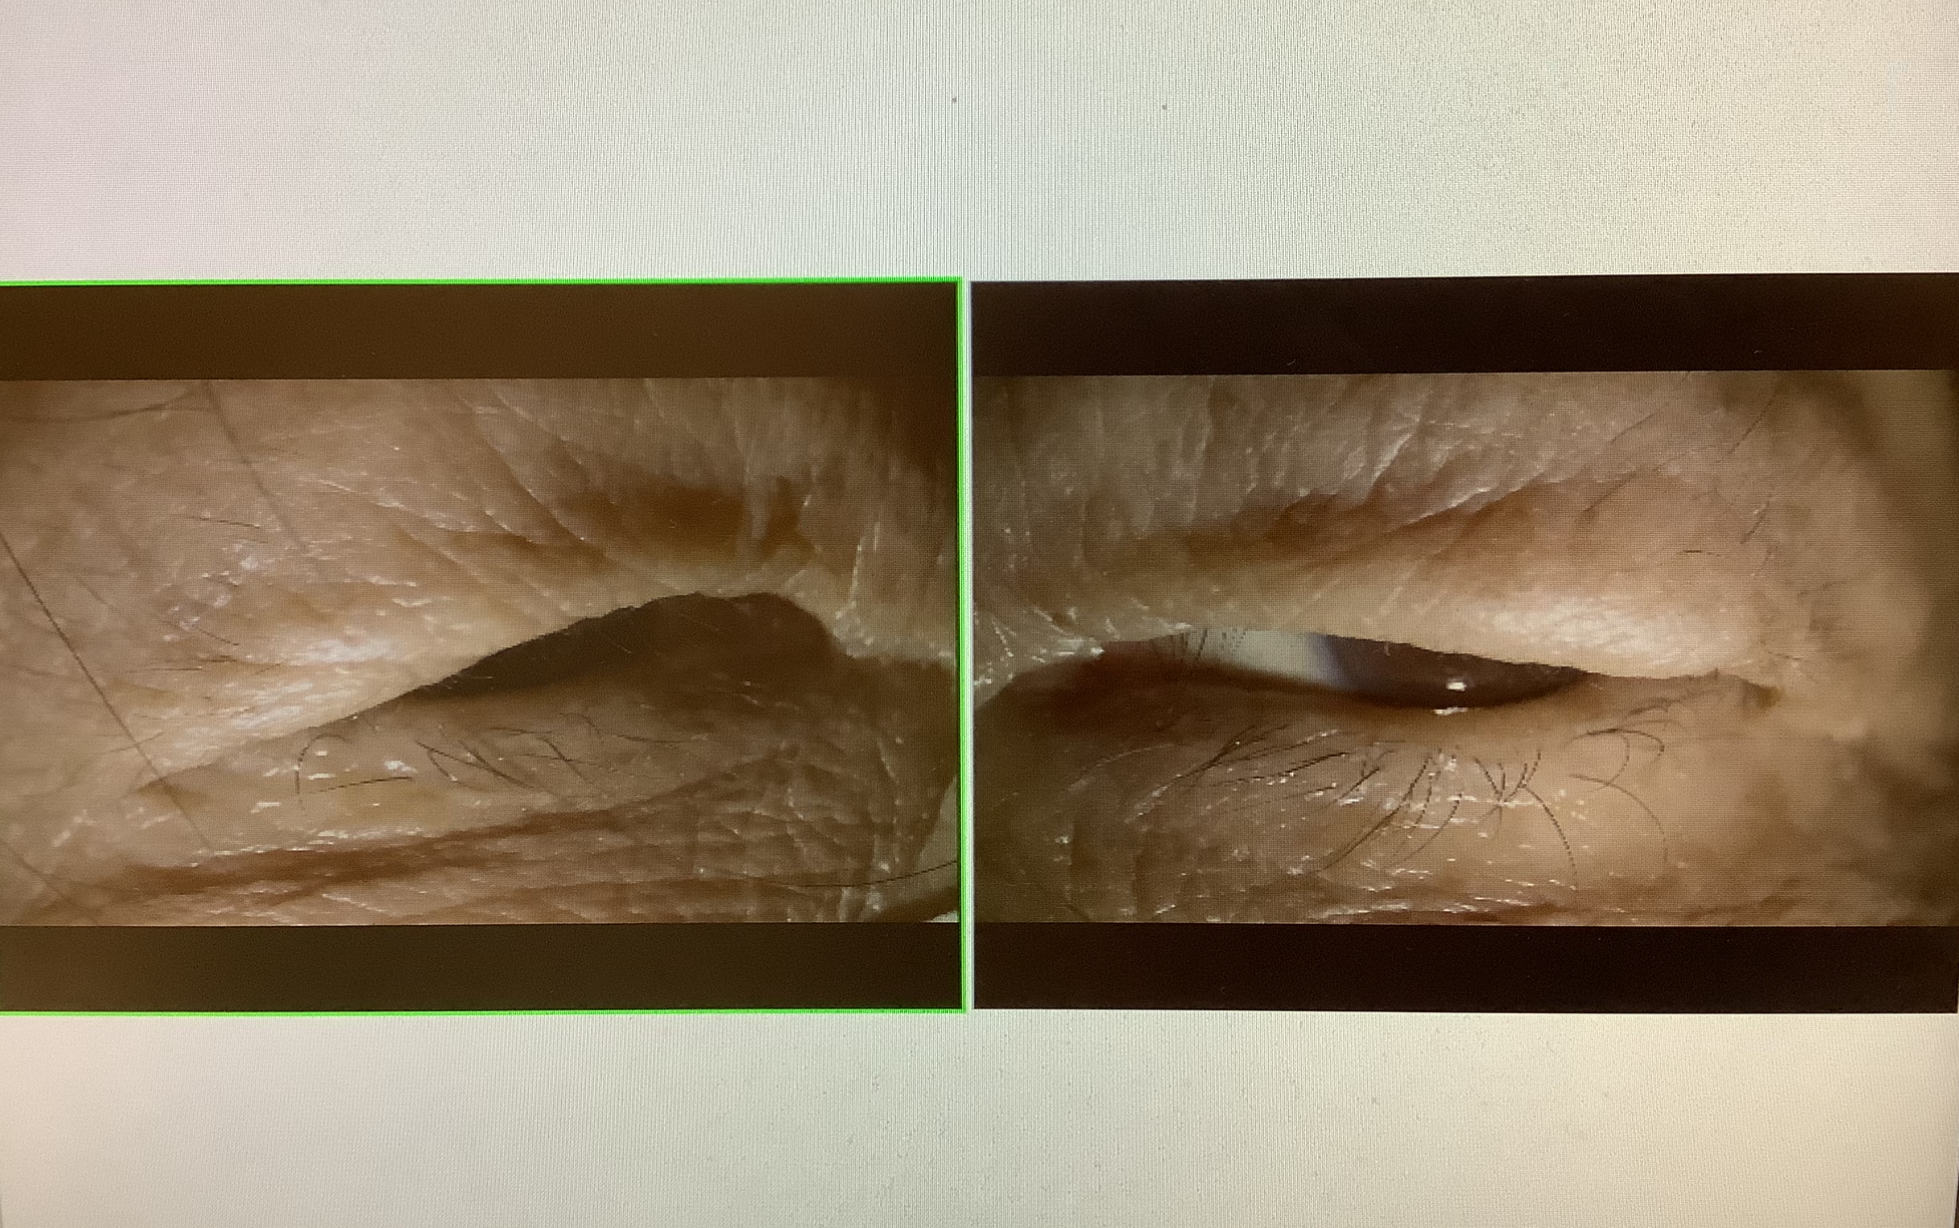

↑お母さまのまぶたの写真。これだけ眼が隠れると、手術した方が楽になると思います。

今回の患者さまもお母様に比べると、眼瞼下垂の程度はずっと軽いですが、困り具合としてはお母様以上と思われ、お二人とも手術の申し込みをさせていただきました。